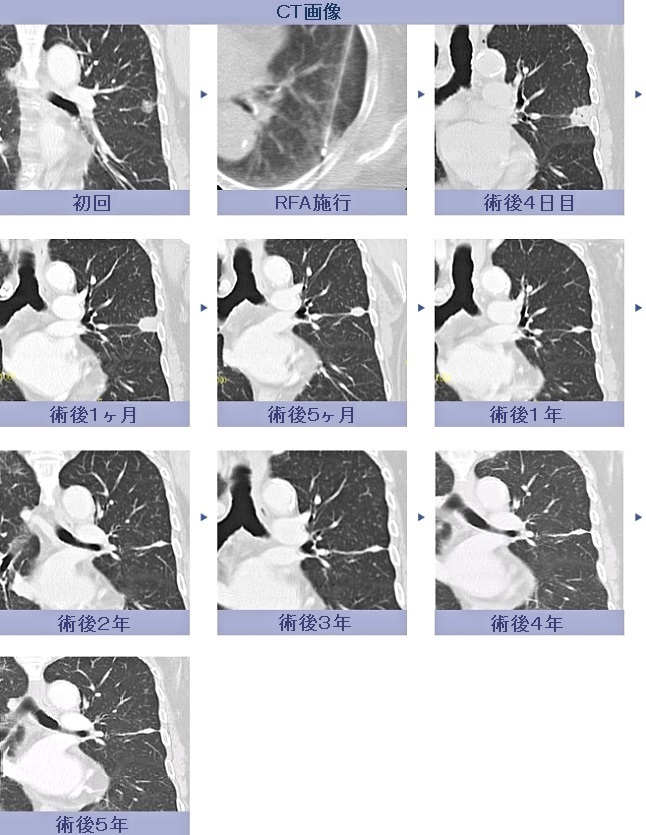

[肺がん] (RFA施行例)

肺RFA

(肺がんに対するラジオ波焼灼治療)